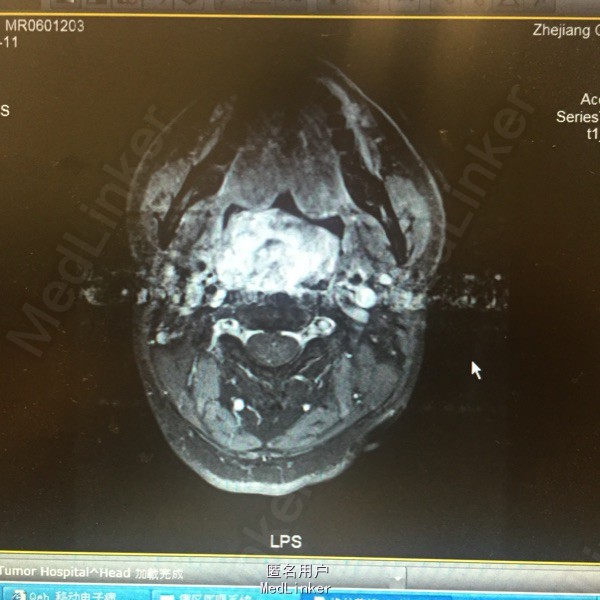

患者男性30岁。因进食困难伴吐血20天入院。患者8年前曾因鼻咽癌行放化疗,放疗资料遗失。近来出现进食困难,2度呼吸困难,近2周体重下降20公斤。

患者张口呼吸,口咽后壁可见巨大菜花样新生物。MRI提示:鼻咽、口咽巨大肿物向下累及右侧犁状窝。活检提示:首先考虑放疗后继发肌源性或纤维源性软组织肉瘤。

诊断:鼻咽癌放疗后继发软组织肉瘤 入院后行急诊气管切开,留置鼻饲营养管给予肠内营养改善全身情况。肿瘤生长迅速,目前给予表阿霉素及异环磷酰胺化疗,拟化疗后行手术切除。